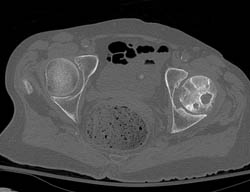

Diagnosis

C-spine Fusion